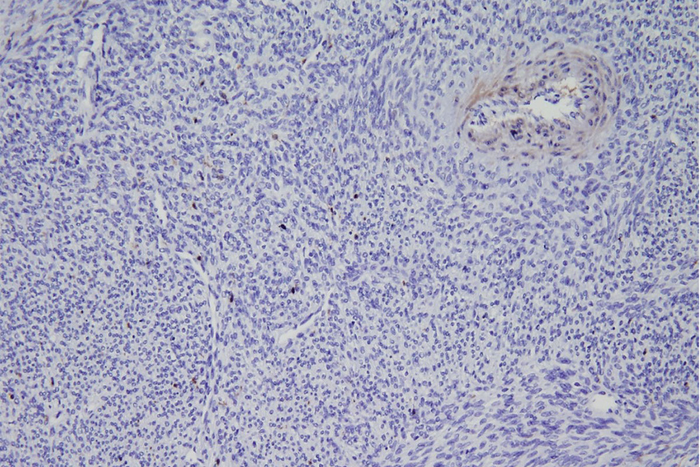

image: A new study from Washington University School of Medicine in St. Louis describes a potential new therapy for synovial sarcoma, a rare tumor of soft tissues. Shown is a biopsy of a synovial sarcoma tumor from a patient. The staining shows that the tumor is missing an important protein called ME1. The missing protein makes this tumor type susceptible to a specific type of cell death that is triggered by a new drug being developed by a Washington University startup. view more

The researchers found that synovial sarcoma is missing an important protein that most tumors rely on to drive their energy metabolism. The absence of this key protein — called malic enzyme 1 (ME1) — forces synovial sarcoma tumors to rely on a different metabolic pathway, which makes it uniquely vulnerable to the inhibition of that alternate pathway. The investigational drug ACXT-3102 interferes with this alternate route. The interference causes volatile waste compounds called reactive oxygen species to build up inside the cancer cells. When enough reactive oxygen species build up inside, the cell dies.